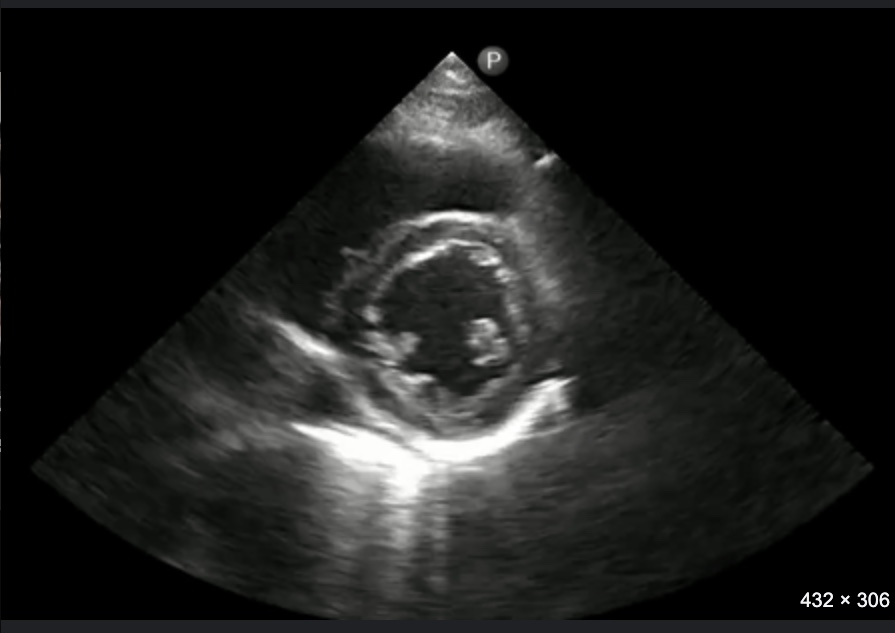

What echocardiographic view will this obtain?

Parasternal short axis (PSAX)

Identify structures and the view of this echo

PSAX